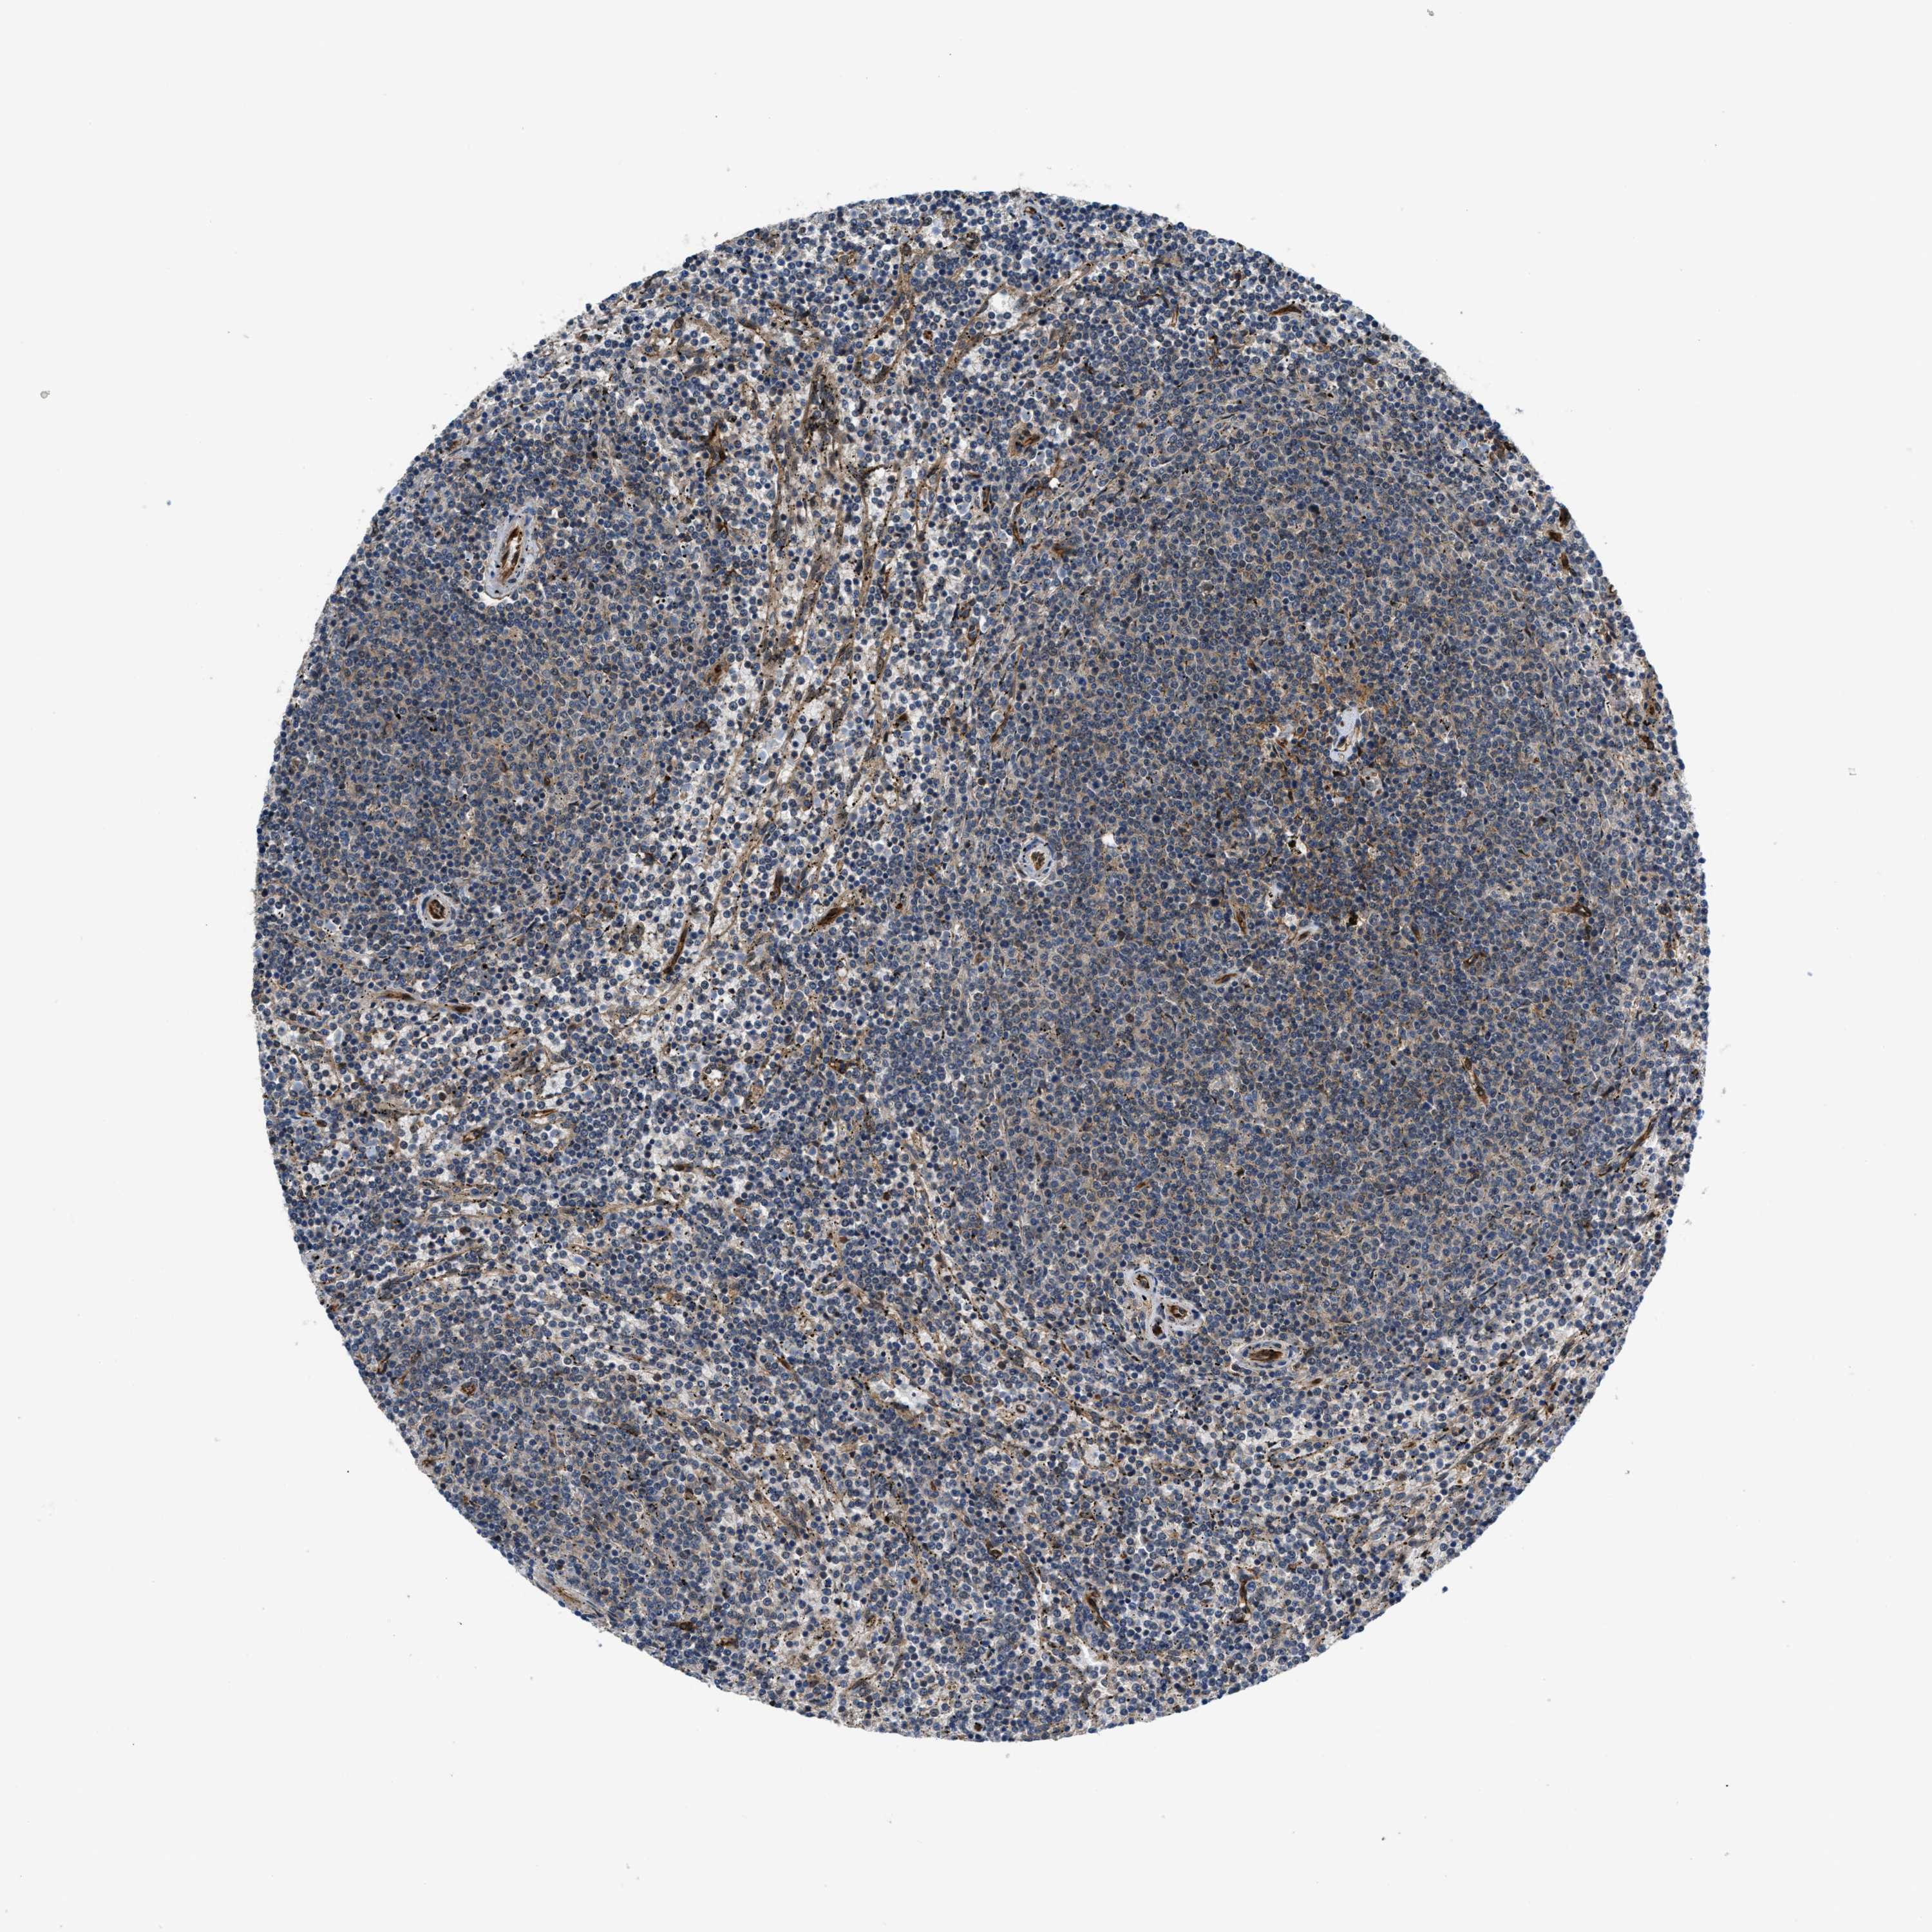

CANCER LYMPHOMA Show tissue menu

LYMPHOMA - Protein expressioni

A mouse-over function shows sample information and annotation data. Click on an image to view it in a full screen mode. Samples can be filtered based on level of antibody staining by selecting one or several of the following categories: high, medium, low and not detected. The assay and annotation is described here.

Antibody stainingi

Antibody staining in the annotated cell types in the current human tissue is reported as not detected, low, medium, or high, based on conventional immunohistochemistry profiling in selected tissues. This score is based on the combination of the staining intensity and fraction of stained cells.

Each image is clickable and will lead to virtual microscopy that enables deeper exploration of all samples and also displays staining intensity scores, fraction scores and subcellular localization as well as patient and tissue information for each sample.

Antibody HPA016867

Antibody HPA018271

Hodgkin's disease, NOS

Malignant lymphoma, non-Hodgkin's type, High grade

Malignant lymphoma, non-Hodgkin's type, Low grade